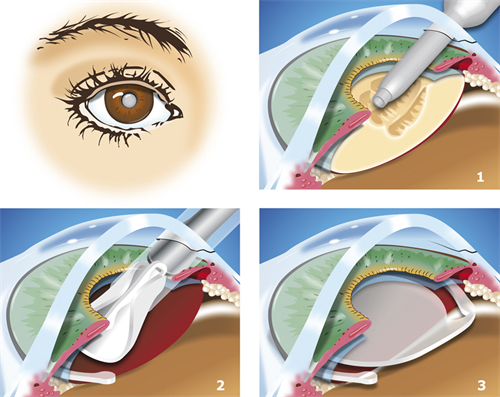

白内障超声乳化术:6800-12800元(不同晶体选择)

优势项目:白内障手术(使用进口晶体时比私立医院低30%)

特殊提醒:每周二下午的"银发关爱日"提供免费白内障筛查